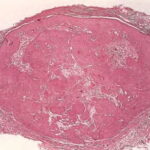

Inverted follicular keratosis = التقران الجرابي المقلوب